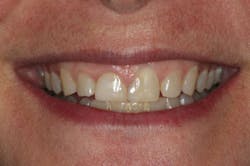

We digitally analyze our esthetics and smile design using the Dawson Diagnostic Wizard (the Dawson Academy). One of our biggest esthetic concerns in this case was caused by a functional issue. As you can see in the photos (figures 1 and 2), the patient has significantly more attritional wear on the right side versus the left. Due to the wear, the right anterior teeth have suffered from more compensatory eruption than the left, which results in uneven gingival architecture and esthetically displeasing length-to-width ratios of the anterior teeth (figures 3 and 4).